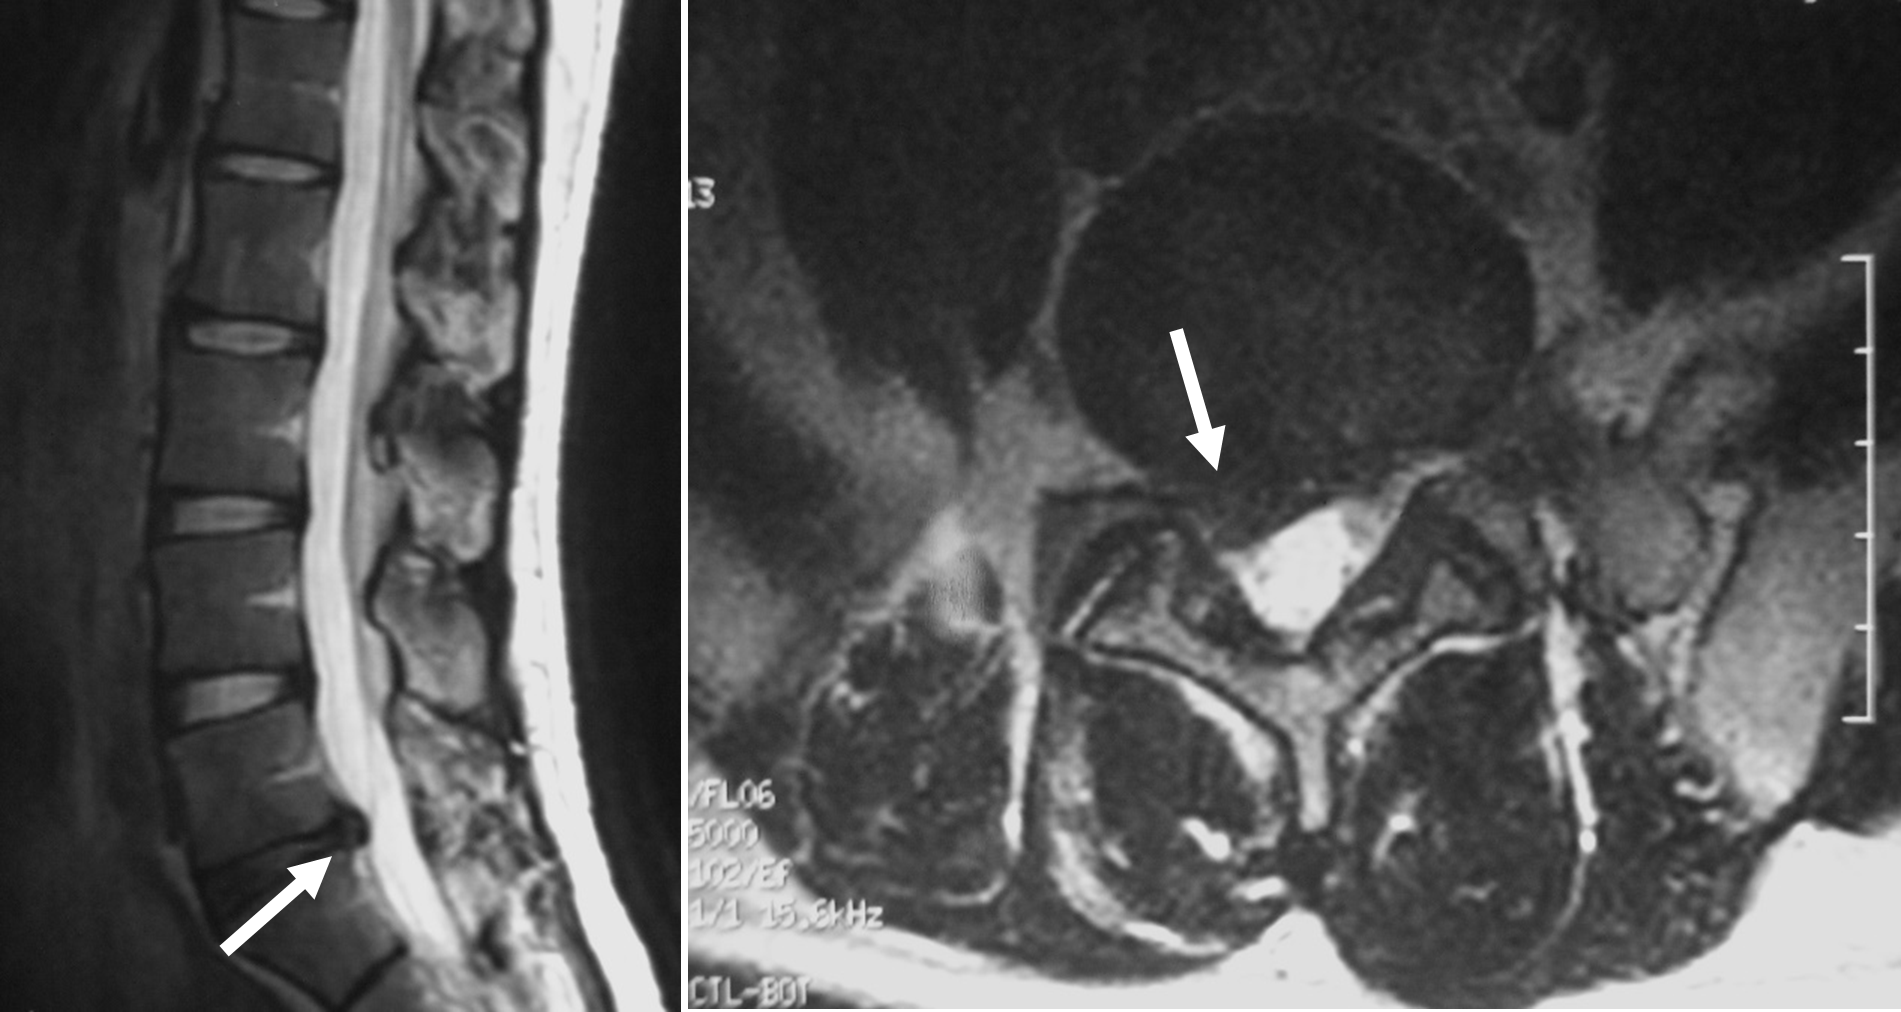

髄核の部分が線維輪の裂け目から押し出され、背後の脊髄や神経根を圧迫する状態を椎間板ヘルニアと呼びます。